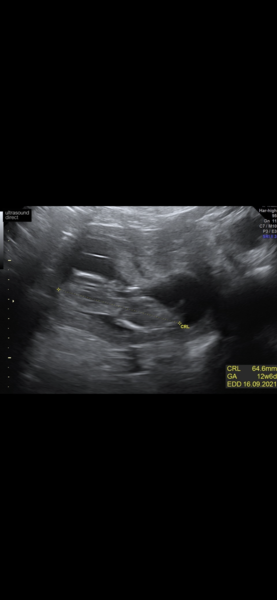

And these are my window to the womb ones from 2 days earlier at 12+4

Private Scan- Clinic Recommendations